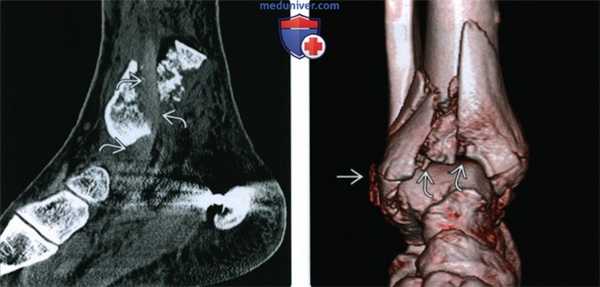

(Слева) При КТ в сагиттальной плоскости в мягкотканном режиме определяется интерпозиция сухожилия задней большеберцовой мышцы (ЗВМ) между отломками дистальною метаэпифиза большеберцовой кости.

(Справа) При КТ на 3D-реконструкции визуализируется передняя поверхность голеностопного сустава. Результатом оскольчатого перелома дистального метаэпифиза большеберцовой кости стало ее укорочение по сравнению с малоберцовой костью. Перелома диафиза малоберцовой кости нет, однако выявляется отрывной перелом области прикрепления удерживателя сухожилий малоберцовых мышц. На томограммах в аксиальной плоскости в мягкотканном режиме (не показаны) обнаружен вывих сухожилий малоберцовых мышц.